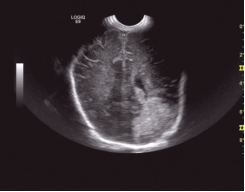

5、盆底超聲及四維子宮輸卵管造影

盆底超聲檢查為盆底肌肉松弛、尿失禁、子宮、直腸、膀胱脫垂、性功能障礙的女性患者及時(shí)發(fā)現(xiàn)盆底結(jié)構(gòu)的形態(tài)學(xué)變化,是診斷盆底功能障礙首選的影像學(xué)方法。

四維子宮輸卵管造影診斷輸卵管通暢性的準(zhǔn)確性高,沒有輻射損傷,不損害卵巢功能,一般2周后即可備孕,可同時(shí)幫助診斷宮腔粘連、疤痕、息肉、肌瘤、子宮先天發(fā)育畸形等疾病。